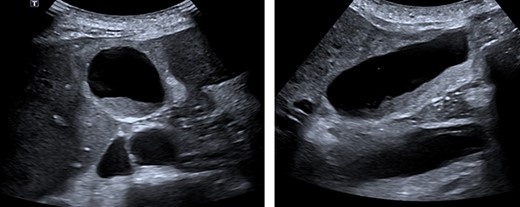

During cholecystectomy, extensive carcinoid metastases were encountered (Figure 2). To perform the operation laparoscopically required retraction of the left liver lobe. However, the liver was stiff and inflamed making exposure of the biliary tree difficult. The gallbladder was mobilized, a critical view of safety and an unremarkable intraoperative cholangiogram was obtained. The length of the operation was 1 h and 35 min. Histopathology of the gallbladder showed benign, chronic outlet obstruction, patchy serosal mixed inflammation and one lymph node containing metastatic disease.

Extensive hepatic metastatic disease. An inelastic liver edge and inflamed gallbladder was encountered with adhesions.